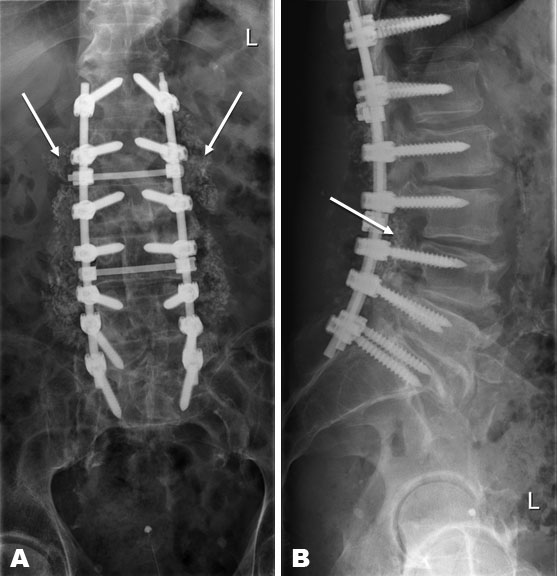

In the short term, five days after the discharge from the previous admission, the patient was readmitted with an increase in back pain, fever (temperature above 38.5°C) and increased infection parameters (sedimentation unknown, Hb 7.4 mmol/L, L 21.4 × 109 mmol/L, CRP 326 mg/L). In suspicion of deep infection, the patient underwent debridement with leaving behind 180 Gentamycin beads (3 times 60 beads). Cultures were taken perioperatively. Postoperatively, intravenous treatment with Cefazoline (3 dd 1000 mg) was started. Based on positive cultures (Staphylococcus epidermidis), Vancomycin was started intravenously based on blood levels, given resistance to Flucloxacillin and Cefazoline. In addition, Rifampicin (2 dd 450 mg) was started with a dry wound. Under antibiotic treatment, the infection parameters decreased steadily. However, a revision operation (Table 2) was performed in the event of sustained wound leakage and in situ beads. A debridement was carried out with the removal of the Gentamycin beads and again with the cultivation of cultures. The previous spondylodesis was extended to level Th12 (Th12-S1) with a 20 cc bioactive glass (2 × 10 cc). The patient recovered quickly postoperatively. Wound healing occurred on day 17. X-ray control showed a good position and fixation of the material (Figure 1A and Figure 1B). With antibiotic treatment, the infection parameters decreased. In clinically good condition, the patient was discharged with oral antibiotics, Minocycline (2 dd 100 mg) and Rifampicin (2 dd 450 mg). In total, the patient was treated for three months due to the presence of osteosynthesis material in the body.

Figure 1: First X-rays of the lumbar spine, anterior-posterior (A) and lateral (B). Bioactive glass visible in posterolateral gutter.

Figure 2: X-rays of the lumbar spine, three months postoperatively, anterior-posterior (A) and lateral (B). Bioactive glass visible in posterolateral gutter.